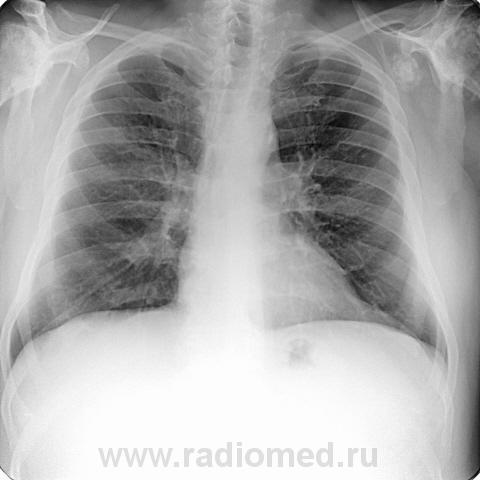

Пациент 60 лет, при прохождении проверочной флюорографии  обнаружены изменения со сторны плечевых суставов.Водитель троллейбуса.Страдает избыточной массой тела, люмбальгией, артороз коленных суставов.Непосредственно жалобы на плечевые суставы в медицинских документах не отражены. Какое будет мнение у коллег?

Александр, конечно надо доснять плечевые суставы... Из того, что есть: видимые отделы плечевых костей выглядят довольно симметрично, хотя слева и похуже, думаю - артроз. Весьма настораживает левая лопатка на предмет хондросаркомы

Уважаемый Александр, приходиться признать, что на цифровой рентгенограмме легких изменения плечевых суставов видны лучше, чем на "обрезаных" и недоэкспонированых снимках суставов. По имеющимся данным могу только сказать, что деф. артроз с кистовидной перестройкой структуры есть. Под хрящевой опухолью (возможно - хондросаркома) левой лопатки я имела в виду тень, отмеченую красными стрелками, которая в поле снимка не вошла. Моя вина - в силу специфики работы такие узкоформатные снимки давно были вредными, т.к. очень часто патология остается за пределами снимка. Остается рекомендовать рентгенография левой лопатки в прямой передне-задней и косой проекциях, а лучше - КТ...